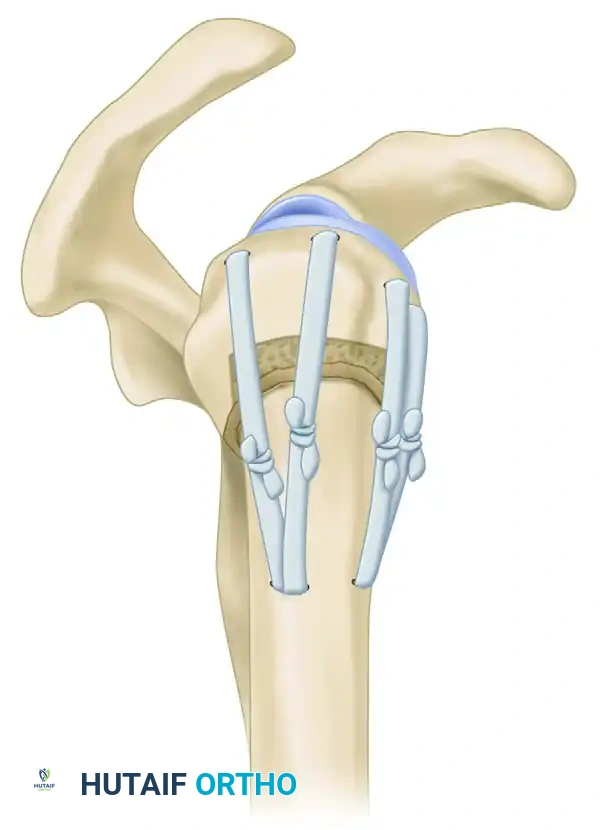

4. Proximal and Distal Locking

- Proximal Locking: Utilize the outrigger device to insert the proximal locking bolts. These bolts often target the humeral head and the lesser/greater tuberosities.

- Soft Tissue Protection: When making stab incisions for the proximal locking screws, carefully spread the soft tissues bluntly down to the bone using a hemostat. This blunt dissection is vital to avoid injury to the axillary nerve, which crosses the lateral humerus in this vicinity.

- Distal Locking: Depending on the nail design, distal locking is performed either via a targeting jig or a freehand perfect-circle fluoroscopic technique. Ensure the anterior structures (biceps, musculocutaneous nerve) are protected during anterior-to-posterior distal locking.